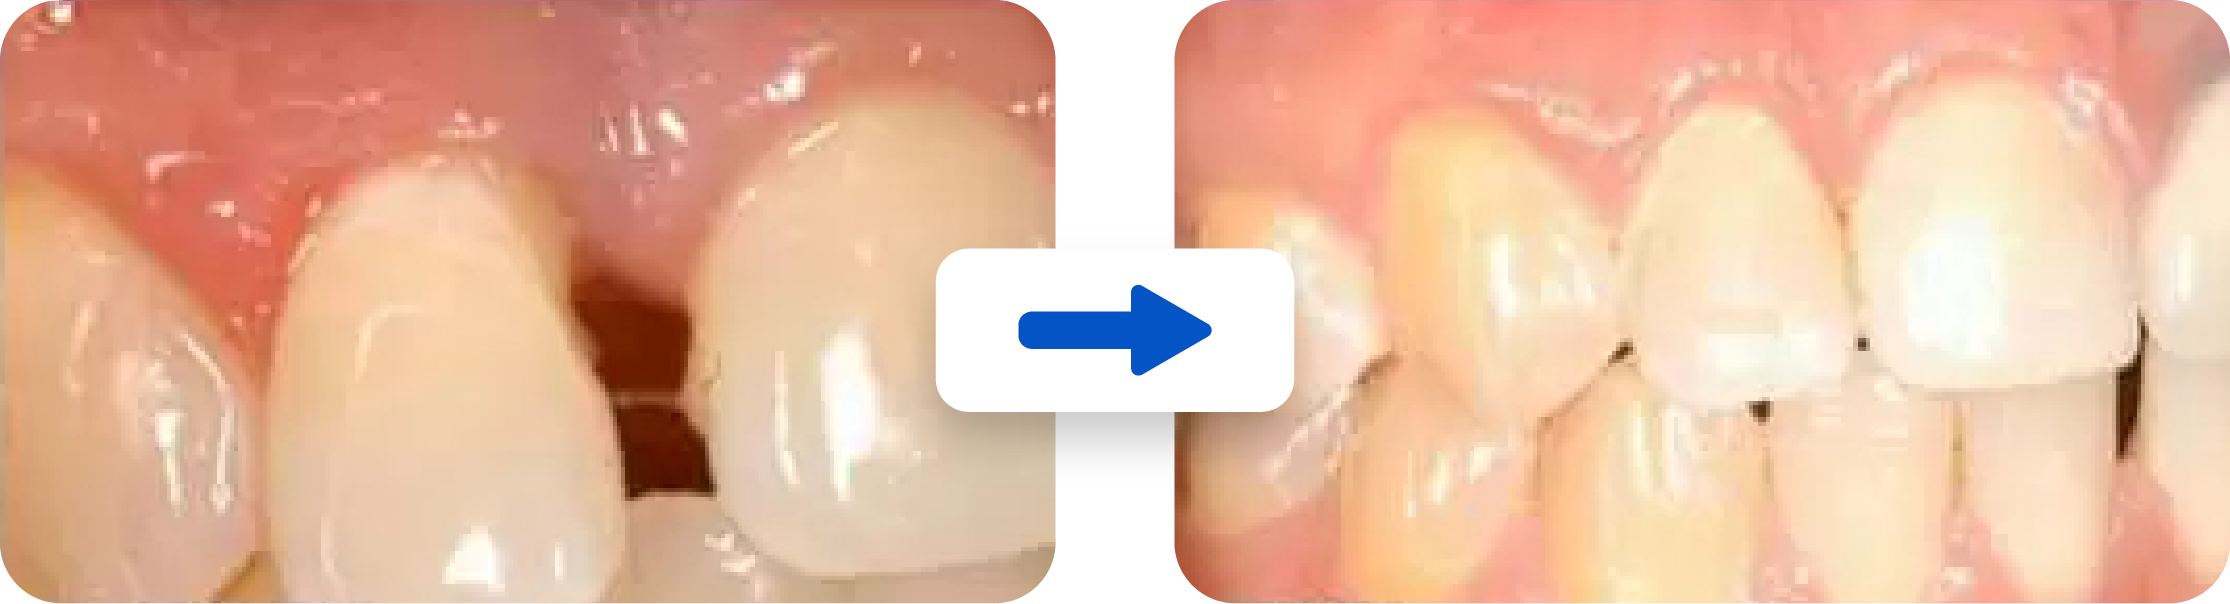

- Full Mouth Reconstruction to replace worn or damaged crowns, fillings, and dental bridges which may be adversely affecting the bite. Dental implants and/or aesthetic crown lengthening may also be used to create a smile that is functional as well as beautiful.

- Reconstruction of badly worn and damaged teeth with crowns and bridges may also help. This may involve a full mouth reconstruction (also called a smile makeover). Reconstruction of badly worn and damaged teeth may involve esthetic crown lengthening as well as dental implants.